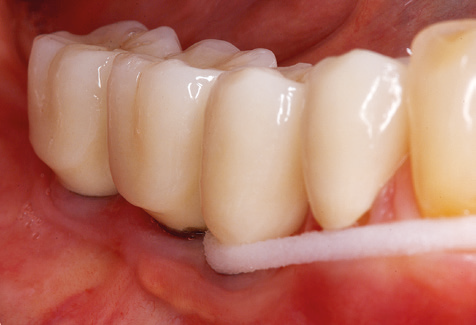

Good illumination of the working field facilitates the process considerably. The system used by the authors achieves this thanks to a 5x LED ring integrated in the handpiece. Naturally, a range of working tips for different indications is also offered. A straight, universally employable tip is the basic instrument required for machine cleaning of natural teeth (Fig. 5a and b). Curved tips, which allow access to exposed furcations, are also available for hard-to-reach areas in the posterior region (Fig. 6).

Fig. 4: Flexible probes with millimetre markings are recommended for the probing of dental implants (e.g. Colorvue Kit PCV11KIT6, Hu­Friedy). – Fig. 5a and b: A straight working tip (1P, W&H Dentalwerk Bürmoos GmbH) is a suitable instrument for use on all natural teeth. – Fig. 6: Curved working tips (3Pr/3Pl, W&H Dentalwerk Bürmoos GmbH) lend themselves to the processing of difficult-to-reach areas of the tooth and root surfaces (e.g. furcations). – Fig. 7: The tapered, hexagonal implant cleaning tip (1I, W&H Dentalwerk Bürmoos GmbH) permits atraumatic and efficient cleaning of the crown and abutment surfaces. – Fig. 8: Titanium and carbon curettes are suitable instruments for the manual cleaning of the implant surfaces.